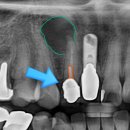

Dentistry, Combination ART & SCIENCE(20240204)

Dentistry, Combination ART & SCIENCE(20230914)

Dentistry, Combination ART & SCIENCE(20241216)